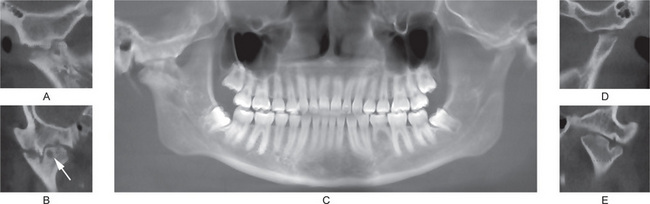

Radiographic examination reveals periosteal new bone formation that can be quite florid and subsequently becomes compact causing pronounced cortical thickening (Fig. 17-28). The periosteal new bone is seen in bones underlying areas of soft tissue swelling. The distribution is patchy and asymmetric but is multifocal, although cases of monostotic involvement have been reported. The mandible is almost invariably involved and other commonly affected areas include the clavicles, ribs and long bones of the limbs. Typically, the periosteal new bone or periosteal ‘cloaking’ is confined to the diaphyses of the long bones, sparing the metaphyses and epiphyses. There are a few reports of lytic areas affecting the skull vault and facial bones but this is uncommon. The spine, phalanges and pelvis are hardly ever involved. Increased uptake of radioisotope from a radioisotope bone scan shows areas of involvement before radiographic changes are present.

The maxilla exhibits progressive enlargement, the alveolar ridge becomes widened and the palate is flattened (Figs. 17-29, 17-30). If teeth are present, they may become loose and migrate, producing some spacing. When the mandible is involved, the findings are similar, but not usually as severe as in the maxilla. As the disease progresses, the mouth may remain open, exposing the teeth, because the lips are too small to cover the enlarged jaw.

Figure 17-29 Osteitis deformans.

There is diffuse enlargement of the maxilla and thickening of the dentulous (A) and edentulous (B) alveolar ridge. In addition, tipping of the teeth due to enlargement of the maxilla is obvious. (B, Courtesy of Dr Robert J Gorlin)

Figure 17-30 Paget’s disease.

Note the enlargement on the right maxilla. The patient was unable to use his denture.